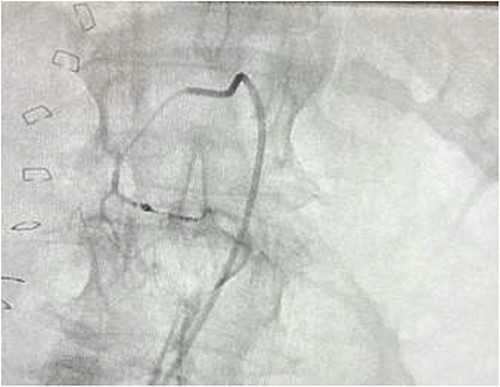

The on-call interventional radiology team performed a successful embolization. A 6-French Sheath was passed through the left common femoral artery, and a 5-French Sim-1 catheter was advanced into the coeliac and common hepatic artery. A 2.4 French Direxon microcatheter was advanced into a branch of the superior mesenteric artery at the site of bleeding. Successful coil embolization with a 2 mm × 2 mm concerto micro coil was performed. A satisfactory angiographic result with DYNA-CT, also known as modern C-arm CT or cone-beam CTA, showed no extravasation.